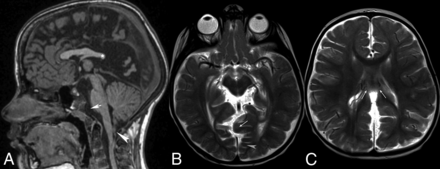

CM-1.5. Sagittal T1WI and T2WI of the cervical and upper thoracic spine (A and B) show obex herniation below the foramen magnum, with medullary kink (arrowhead).